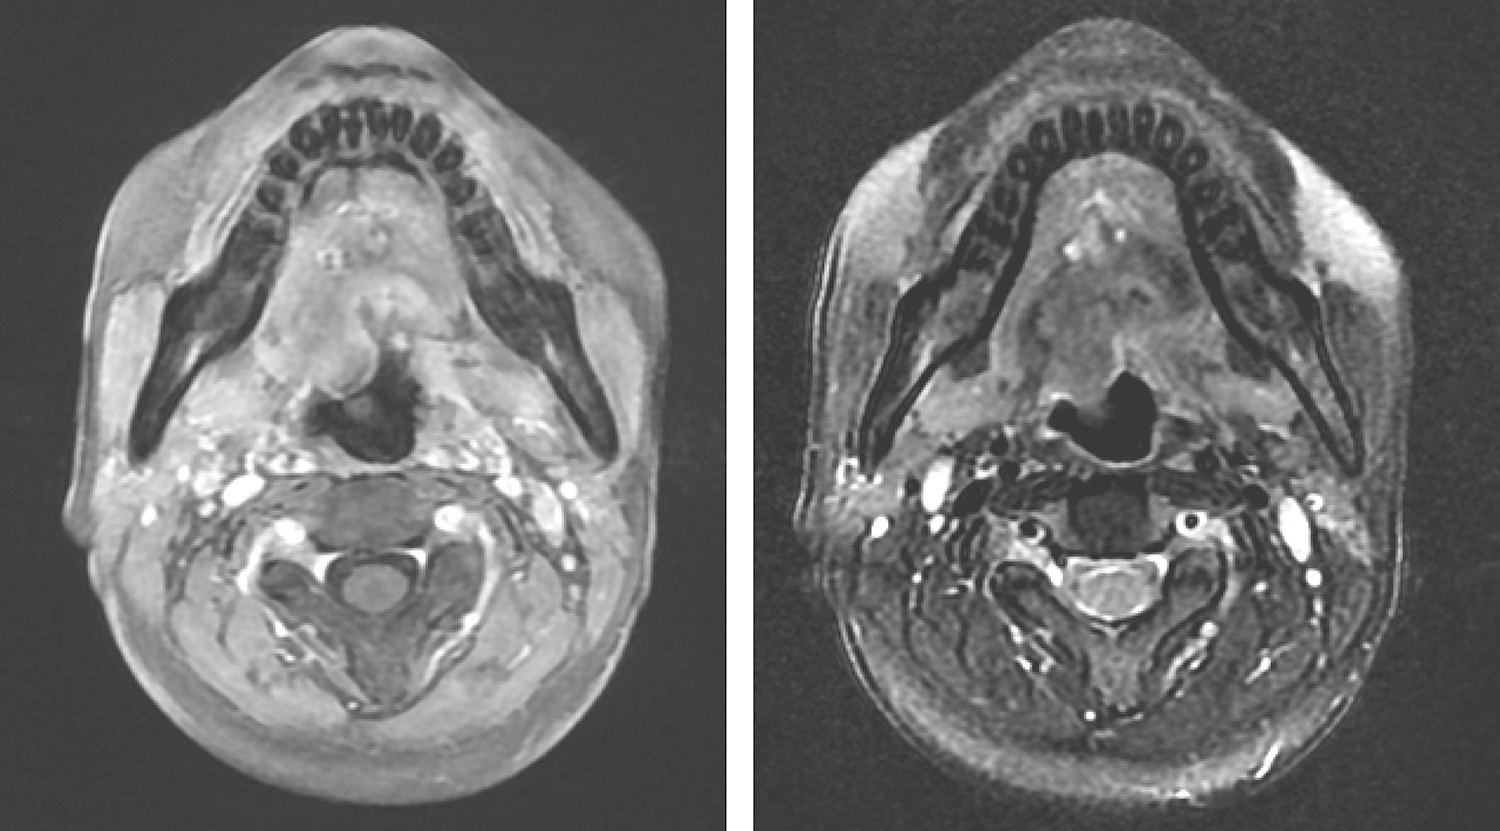

胸部CT:右肺肿块较前增大,左肺尖结节,右肺及左肺上叶多发斑片,条索影,右侧胸膜增厚并局部结节状改变,右侧少量胸腔积液,与前片相仿;肝右叶低密度灶增大,胰尾部低密度灶相仿,均可能为转移灶(图1)。

图1 患者自2011年5月确诊晚期肺腺癌,依次使用吉西他滨+顺铂化疗、吉非替尼、阿法替尼和奥希替尼靶向治疗,均获得长期缓解;复查胸部CT(2016-09-06)提示右肺上叶后段病灶稳定,右肺中叶病灶较前显著增大(白箭),考虑患者奥希替尼治疗后病情进展